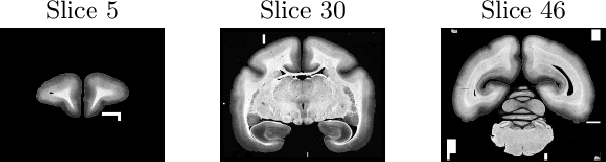

Abstract:Image registration, especially the quantification of image similarity, is an important task in image processing. Various approaches for the comparison of two images are discussed in the literature. However, although most of these approaches perform very well in a two image scenario, an extension to a multiple images scenario deserves attention. In this article, we discuss and compare registration methods for multiple images. Our key assumption is, that information about the singular values of a feature matrix of images can be used for alignment. We introduce, discuss and relate three recent approaches from the literature: the Schatten q-norm based SqN distance measure, a rank based approach, and a feature volume based approach. We also present results for typical applications such as dynamic image sequences or stacks of histological sections. Our results indicate that the SqN approach is in fact a suitable distance measure for image registration. Moreover, our examples also indicate that the results obtained by SqN are superior to those obtained by its competitors.